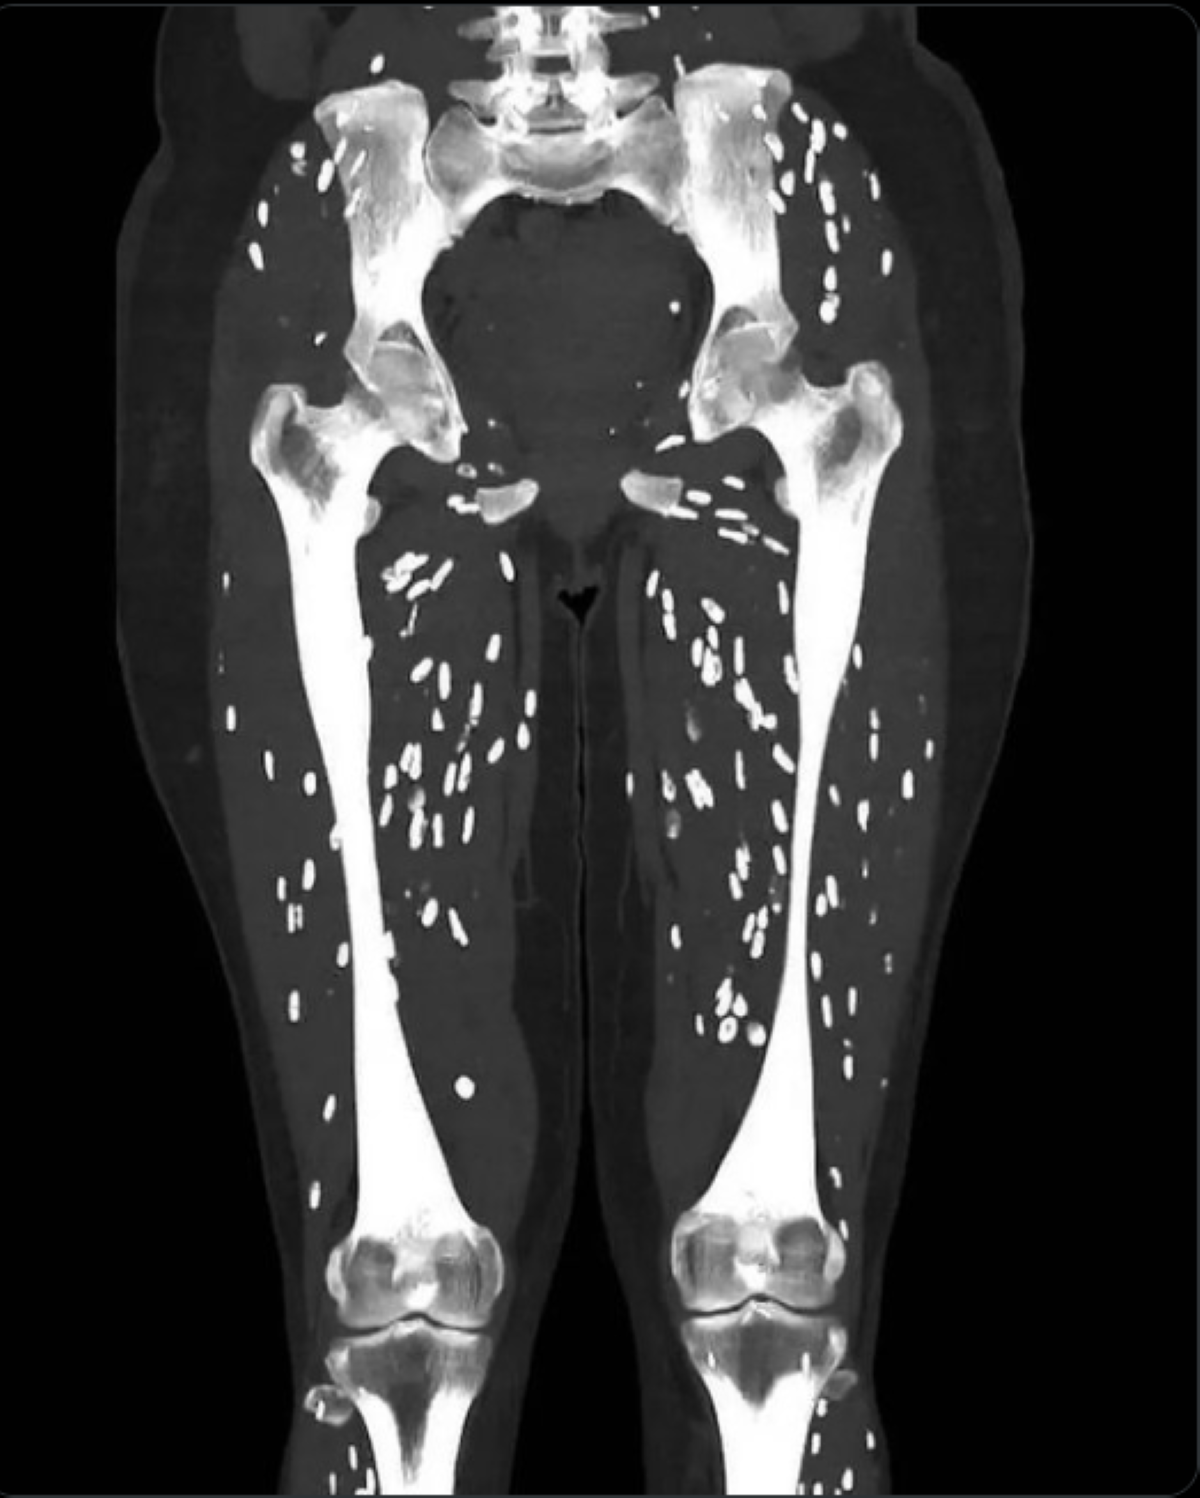

Dr. Sam Ghali, un medic de urgență de la Universitatea din Florida, a postat pe rețelele sociale o imagine cu scanarea CT a unui pacient care prezintă semne evidente ale unei infecții parazitare cunoscute sub numele de cisticercoză.

Această boală apare atunci când larvele unui anumit tip de tenie, Taenia solium, pătrund în țesuturi precum mușchii sau creierul, unde formează chisturi dure calcificate. Aceste chisturi apar ca niște noduli albi, ovali, asemănători cu boabele de orez, la scanările medicale și pot fi simțite sub piele ca niște umflături mici.

Deși aceste chisturi sunt în general inofensive, deoarece larvele nu supraviețuiesc în afara intestinului, ele pot cauza probleme serioase dacă ajung în creier, provocând dureri de cap, convulsii, confuzie și chiar o afecțiune gravă numită hidrocefalie, care necesită de obicei intervenție chirurgicală.

Odată ingerate, ouăle eliberează larve care pot migra prin fluxul sanguin către diverse țesuturi, unde sunt ucise de sistemul imunitar și formează chisturi calcificate. Dacă chisturile ajung la ochi, pot provoca tulburări de vedere și infecții.